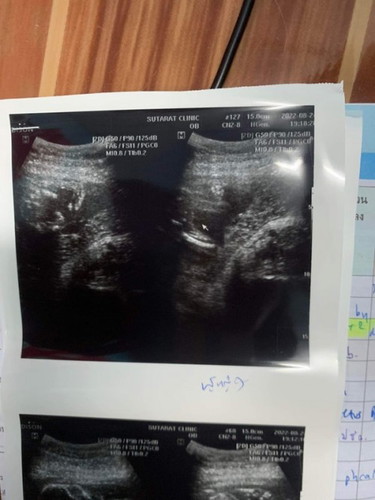

แม่ๆเห็นเป็น ผู้หญิงหรือผู้ชายค่ะ แต่คุณหมอบอกผู้หญิงค่ะ ตรงที่ลูกศรชี้

ผู้หญิงค่ะ ของเราผู้ชายแบบนี้